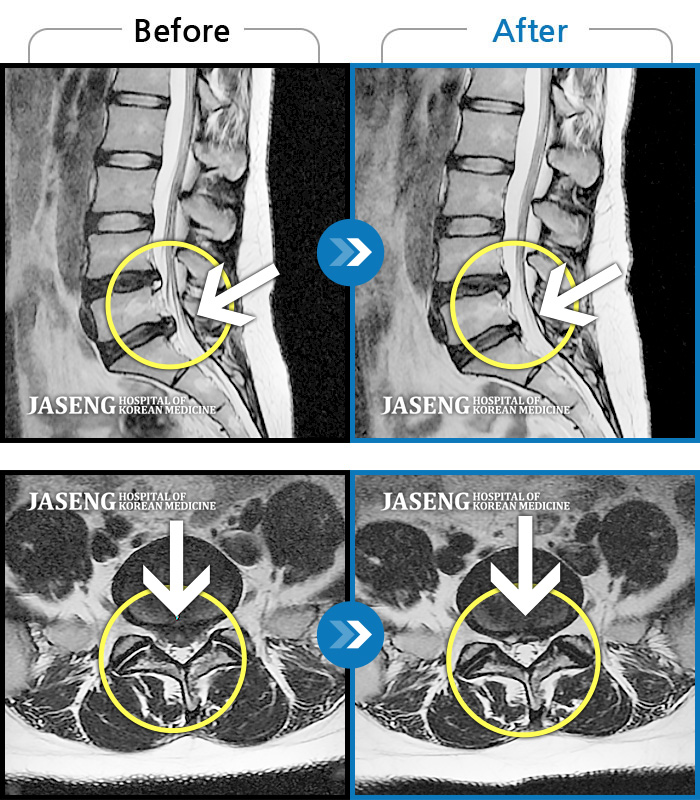

허리디스크

보라매 · 왕오호 원장

좌측 허리 통증 및 좌측 다리 저림

촬영시기

2016.05.21 ~ 2018.04.13

2018.12.28

조회수 692